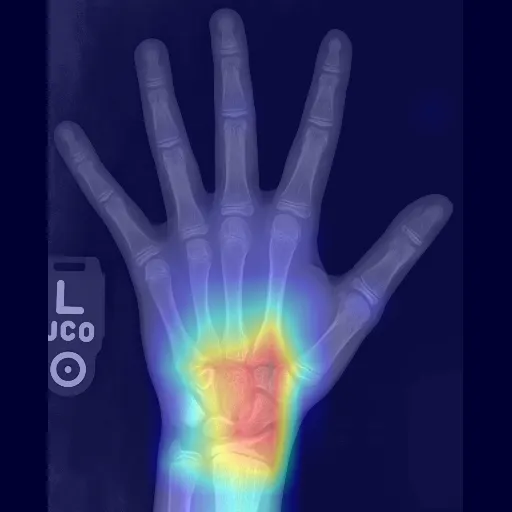

"{""label"": ""14 years"", ""confidences"": null}","The closest Greulich & Pyle bone ages are:

1) 14 years

2) 13 years, 6 months","{""path"": "".gradio/cached_examples/20/Heatmap Image/952c4f43d08373a5d9b6/image.webp"", ""url"": ""/gradio_api/file=/tmp/gradio/dc5bc36643f08e7905a28d3a20853a3709f8a0b566d4f1dae39bed2fb178bca8/image.webp"", ""size"": null, ""orig_name"": ""image.webp"", ""mime_type"": null, ""is_stream"": false, ""meta"": {""_type"": ""gradio.FileData""}}",2024-12-16 11:45:53.910234

"{""label"": ""5 years"", ""confidences"": null}","The closest Greulich & Pyle bone ages are:

1) 5 years

2) 5 years, 9 months","{""path"": "".gradio/cached_examples/20/Heatmap Image/33ead32d7cadc4f26d4b/image.webp"", ""url"": ""/gradio_api/file=/tmp/gradio/e860e2b868e0d01ce87c9802cd5777b6a9bc554743c2ed8bbcb24eb9b9fa6e02/image.webp"", ""size"": null, ""orig_name"": ""image.webp"", ""mime_type"": null, ""is_stream"": false, ""meta"": {""_type"": ""gradio.FileData""}}",2024-12-16 11:45:56.361340

"{""label"": ""11 years, 9 months"", ""confidences"": null}","The closest Greulich & Pyle bone ages are:

1) 12 years

2) 11 years","{""path"": "".gradio/cached_examples/20/Heatmap Image/f2d4910659006b78e8b4/image.webp"", ""url"": ""/gradio_api/file=/tmp/gradio/4f51148a75979962de3db405711cd85b91f7953a5bfd4345b3f75769727a1fc2/image.webp"", ""size"": null, ""orig_name"": ""image.webp"", ""mime_type"": null, ""is_stream"": false, ""meta"": {""_type"": ""gradio.FileData""}}",2024-12-16 11:45:58.619854